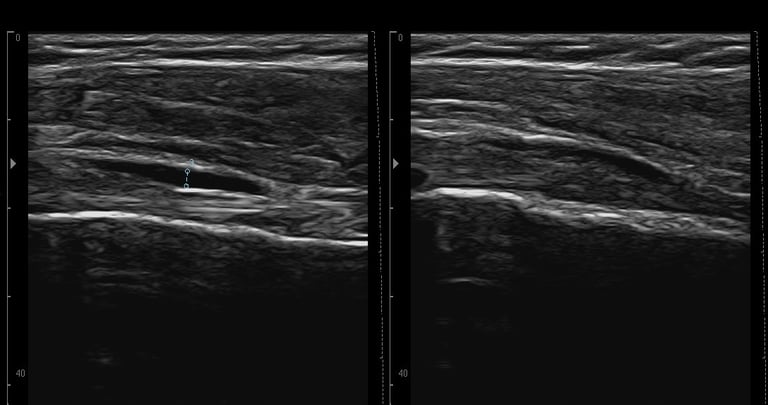

Permette di osservare in tempo reale i tessuti durante il movimento. In questo modo posso analizzare il comportamento muscolare, la qualità del gesto e la risposta dei tessuti a un esercizio. È uno strumento utile per comprendere meglio come ti muovi, personalizzare il trattamento e monitorare i cambiamenti nelle sedute successive

Metodo RUSI

Il metodo RUSI trasforma l’ecografia da semplice strumento diagnostico a partner attivo nella riabilitazione, permettendo di vedere, capire e correggere ciò che accade nel corpo mentre si muove